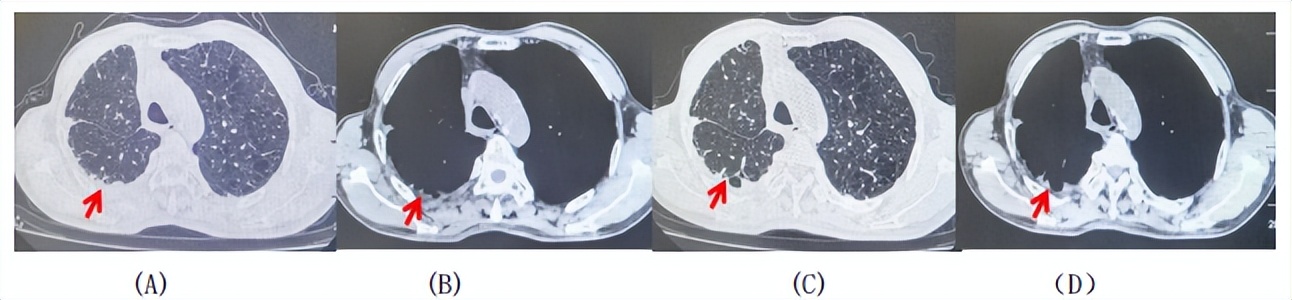

71岁男性,高血压病史20年,口服药物治疗,无糖尿病、心脏病等基础疾病,吸烟史50年,20支/天,已戒1年余,无饮酒史,无肿瘤家族史。2023.11因咳嗽、咳痰行胸CT检查:左肺下叶占位性病变,大小约12mmx8mm(如图5)。2023.11.20行“单孔胸腔镜左肺中下叶切除、肺门及纵隔淋巴结清扫、胸膜粘连松解术”;术后病理:(左肺下叶)结合免疫组化鳞状细胞癌(中、低分化),局部见脉管内癌栓,未见确切神经侵犯,(气管切缘)净。(淋巴结)未见转移癌0/19(4组0/1;5组0/1;6组0/2;7组0/1;9组0/1;10组0/2;11组0/3;12组0/2;13组0/2;14组0/4)。术后分期pT1bN0M0 IA期,术后定期复查。

2024.09.12复查胸部CT示左侧胸膜结节,大者约为27mmx13mm,考虑转移可能性大,纵隔淋巴结增大,恶性?(如图6)。患者行胸膜穿刺活检取病理,结果示(胸膜)结合免疫组化,支持鳞状细胞癌,PD-L1(克隆号28-8)TPS约20%。分期为rT0N2bM1a IVA期,DFS为10个月。2024.09.24起行替雷利珠单抗联合紫杉醇+卡铂方案治疗4周期,复查胸CT评效SD(如图7)。后患者因脑梗塞停止治疗,于综合医院就诊,后未返院复查及治疗。

图5:患者手术前(2023.11)胸部CT肺窗及纵隔窗

图6:患者胸膜及纵隔转移(2024.09)胸部CT肺窗及纵隔窗

图7:替雷利珠单抗联合白蛋白紫杉醇+卡铂治疗4周期后(2024.12)胸部CT肺窗及纵隔窗